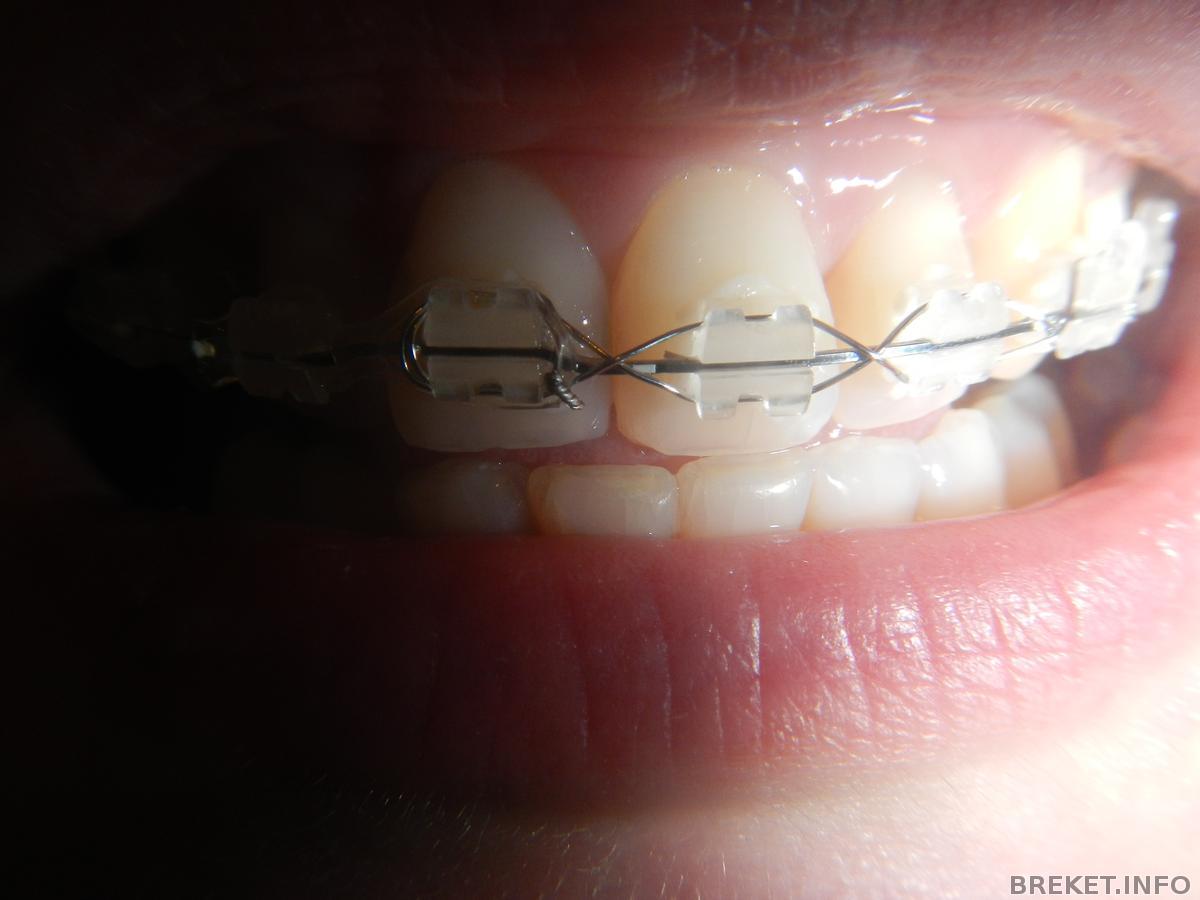

верх стянула проволкой так, что укусить не могла еще вчера...Пока снятие не назначили, но думаю не за горами.